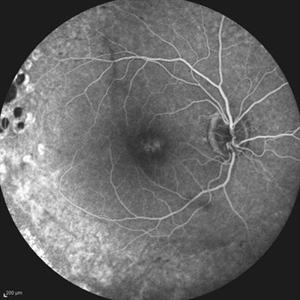

Behcet's Disease Behcet's DiseaseMar 13 2013 by Hamid Ahmadieh, MD Early phase FA of the left eye of a 23-year-old man with retinal vasculitis due to Behcet's disease . Photographer: Solmaz Shahmohammad, Negah Eye Center, Tehran Imaging device: Heidelberg Spectralis Condition/keywords: retinal vasculitis

Behcet's Disease Behcet's DiseaseMar 13 2013 by Hamid Ahmadieh, MD Mid phase FA of the left eye of a 23-year-old man with retinal vasculitis due to Behcet's disease . Photographer: Solmaz Shahmohammad , Negah Eye Center, Tehran Imaging device: Heidelberg Spectralis Condition/keywords: retinal vasculitis